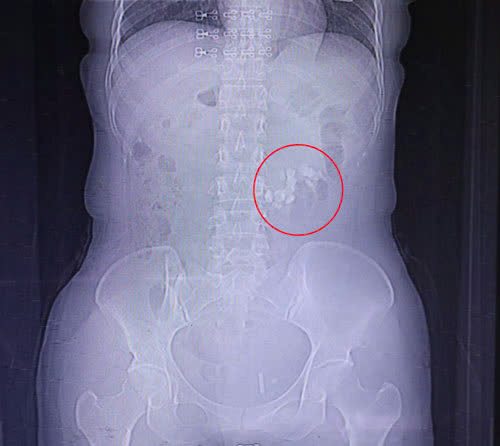

Người bệnh P.T.L. 42 tuổi, Phường Uông Bí nhập viện Việt Nam – Thụy Điển Uông Bí trong tình trạng đau quặn vùng mạn sườn trái, đau lan xuống vùng bụng dưới. Qua thăm khám, siêu âm và CT Scanner, các bác sĩ phát hiện người bệnh có dị dạng thận móng ngựa - một dị dạng bẩm sinh khiến hai thận dính nhau ở cực dưới tạo hình “móng ngựa” kèm theo sỏi thận lớn.

Sỏi thận của người bệnh (Vùng khoanh tròn màu đỏ)

Kỹ thuật tán sỏi qua da - giải pháp hiệu quả cho trường hợp phức tạp

Trước tình hình đó, kíp phẫu thuật đã tiến hành thực hiện kỹ thuật tán sỏi qua da - một phương pháp ít xâm lấn, an toàn và hiệu quả

Ca can thiệp được thực hiện dưới sự hỗ trợ của siêu âm và C-arm. Sau gần 2 giờ, toàn bộ sỏi thận đã được tán vụn và loại bỏ hoàn toàn, không còn cản quang trên hình ảnh kiểm tra sau phẫu thuật. Người bệnh hồi phục nhanh, hết đau quặn, chức năng thận ổn định.